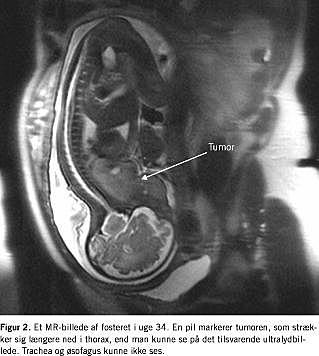

I. En 40-årig, gravid kvinde blev henvist til Rigshospitalet på grund af en 2 cm stor tumor på fosterets hals opdaget ved en 18-20-ugers gennemskanning. Tumoren voksede hurtigt og målte 54 × 48 × 56 mm i uge 33 (Figur 1 ). Fra uge 29 observeredes der tiltagende polyhydramnios som udtryk for afklemning af øsofagus, og der blev foretaget flere aflastende amniocenteser. Ved ultralydsundersøgelser og MR-skanninger i uge 34 fandt man en tumor, der var velafgrænset og heterogen uden store kar, målte 94 × 43 × 60 mm og var beliggende på højre side af halsen (Figur 2 ). Øsofagus og trachea kunne ikke ses og ansås for at være komprimerede. Ved en tværfaglig konference vurderede man, at der var risiko for, at fosteret ville have en kompromitteret luftvej ved fødslen, og der blev planlagt sectio med EXIT-procedure i uge 36 med henblik på at bevare placentafunktionen og etablere frie luftveje før afnavling. Generel anæstesi blev indledt med tiomebumal-fentanyl og vedligeholdt med sevofluran og fentanyl. Uterus blev relakseret med sevofluran, diclofenac og atosiban (oxytocin-receptorantagonist). Blodtabet blev skønnet til at være på en liter, og anæstesien varede ca. 90 minutter og forløb ukompliceret.